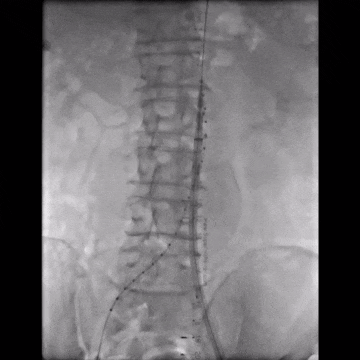

造影示肾下腹主动脉瘤

选用28-14-140mm主动脉覆膜支架

释放短腿(交叉腿)

导丝超选右髂支

右侧延续16-18-140mm髂支

左侧延续16-18-140mm髂支

术中释放右侧髂支后,患者突发腹痛、心率增快、血压下降,造影怀疑右髂动脉破裂,紧急加放髂支并弹簧圈栓塞。